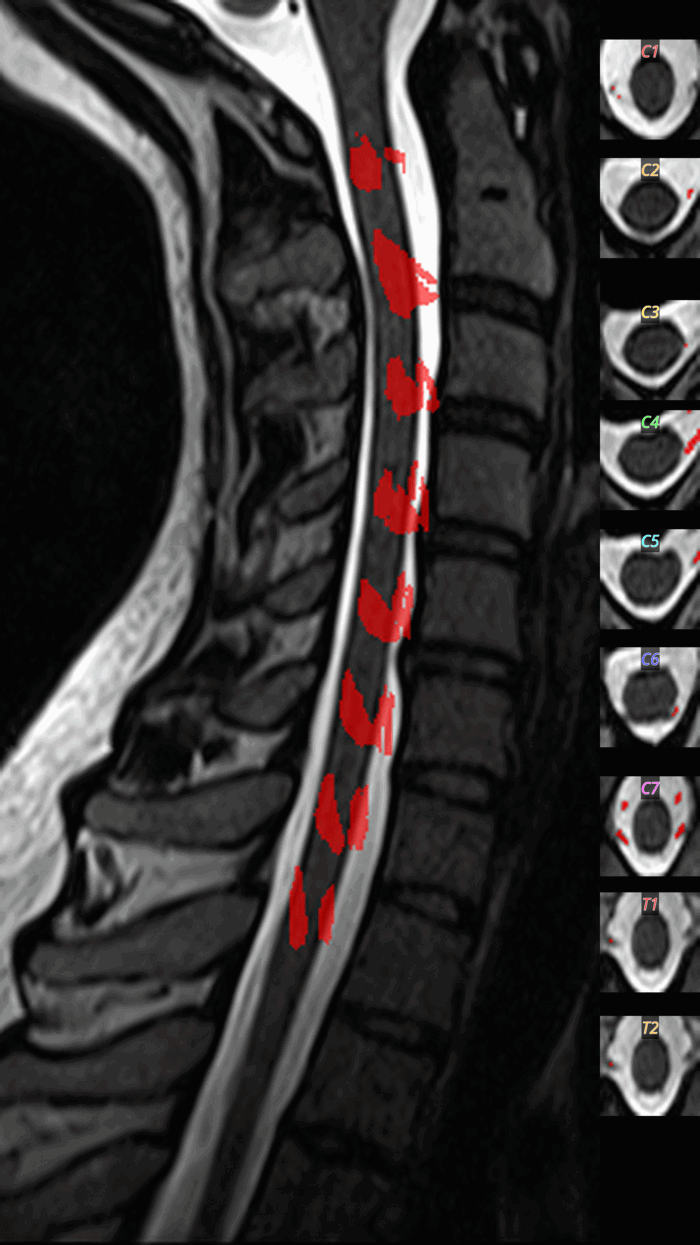

QC: Rootlets Montage

What to look for:

- ✅ Rootlets appear at dorsal-lateral positions

- ✅ Regular spacing along the cord

- ❌ FAIL: Rootlets detected ventrally (false positives)